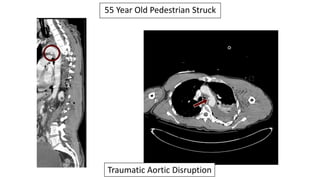

55 Year Old

Pedestrian Struck

Traumatic Aortic Disruption & Multiple Rib Fractures

Traumatic Aortic Disruption

Successfully

Deployed TEVAR